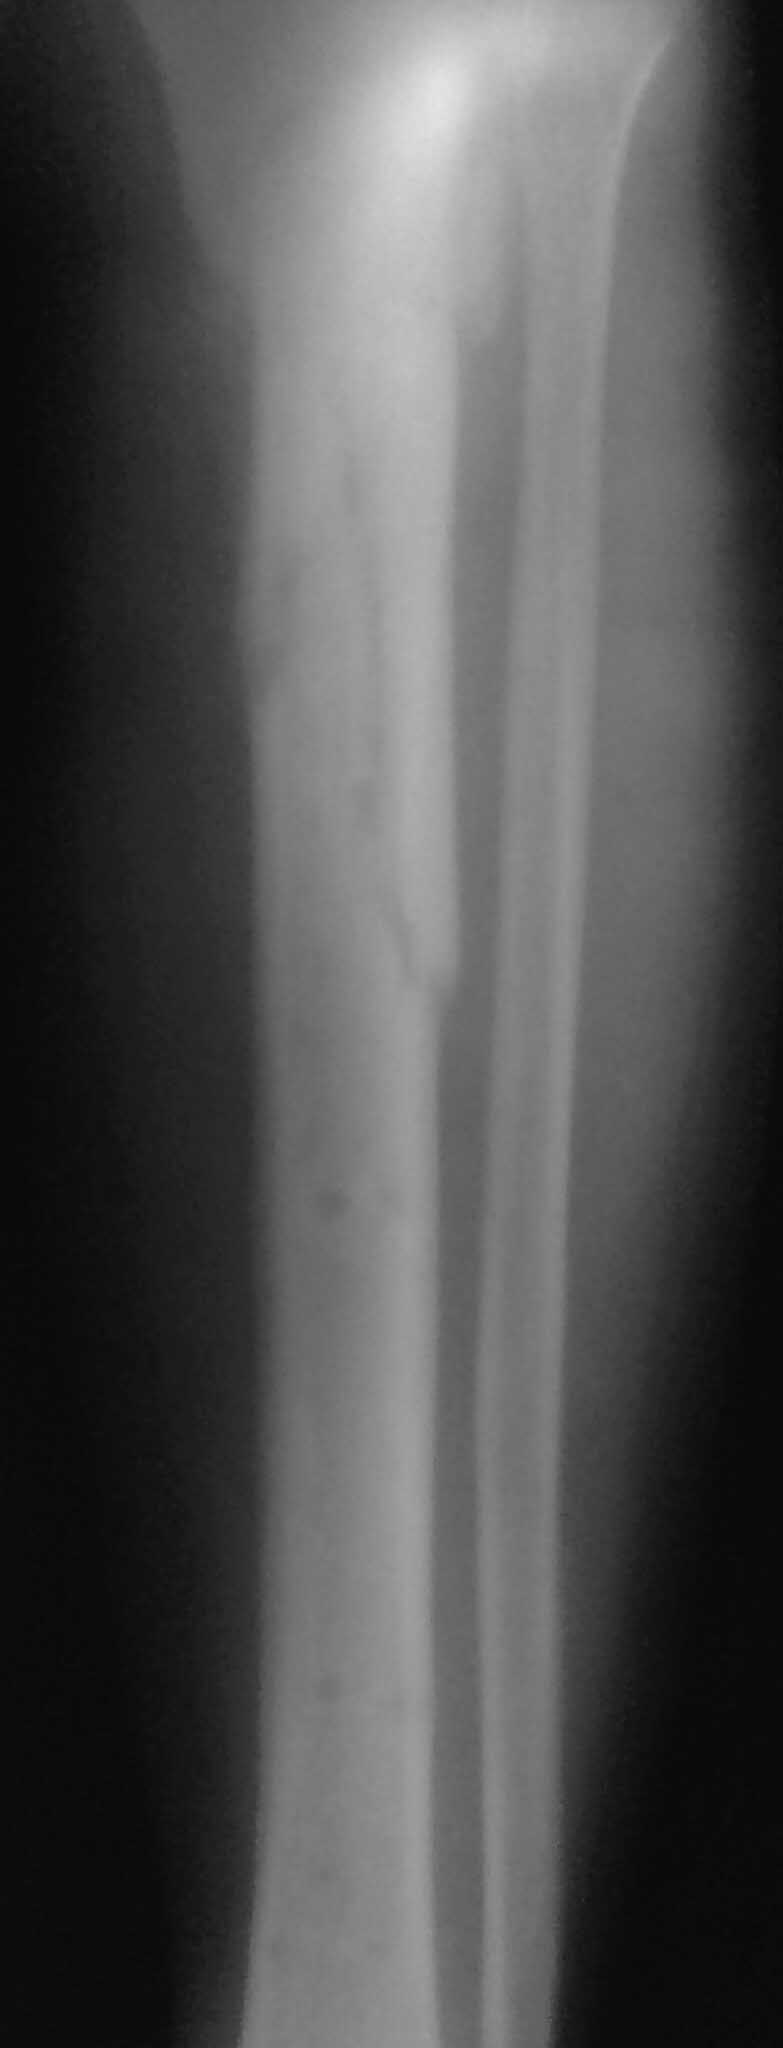

Важны мнения опытных докторов владеющих интрамедуллярным остеосинтезом. Пациент 50 лет.В анамнезе з/оскольч.перелом в/з-с/3 б/б кости. Был в АВФ 9 мес, демонтирован по его словам по поводу спицевой инфекции.также был со слов вскрыт гнойник на передней поверхности голени в зоне ложняка. на данный момент клинически: патол.подвижность в в/з голени и заживающая рана 0,2*4см по передней поверхности голени в зоне ложняка с скудно-умеренным серозным отделяемым( скорее вне зоны проведения спиц). Подвижность -умереннная. Трофических и сосудистых нарушений можно сказать нет. Сгибание в коленном суставе возможно без насилия ок. 50град. Вопрос - как делать? Нам предстваляется два пути: 1.Не дожидаясь заживления раны о/с АВФ,с открыванием ложняка: почистить его+ остеотомия малобрецовой ближе к н/3-с/3 границе. 2.перевязывать рану, после заживления подождать недельки две. Паралельно разрешить приступать на конечность. 2.1Если гной будет то см.вариант1.

Жаль, что нет фасной проекции. Перелом на 2 уровнях, есть искривление костно-мозгового канала. Проксимальный отломок короткий. Вывод: лучше не штифтовать.

3.Перелом на 2 уровнях, есть искривление костно-мозгового канала. Проксимальный отломок короткий.